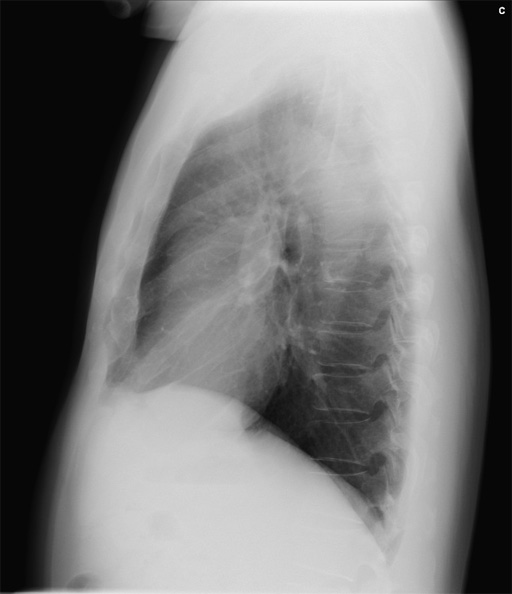

症例7 : 図2 初診時 単純X線写真 (側面像)